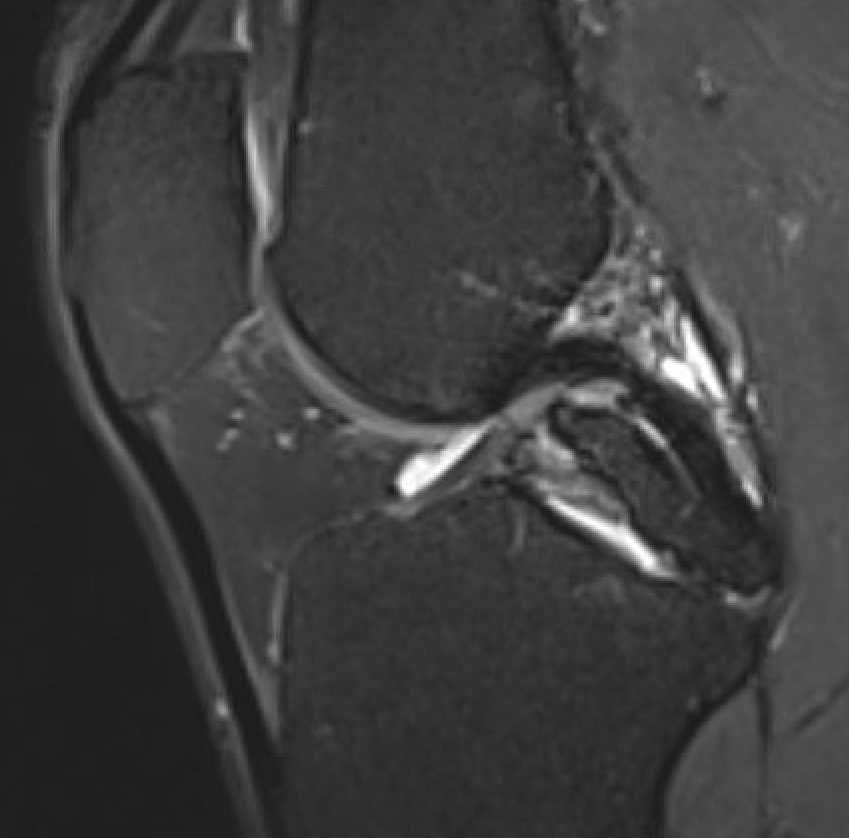

MRI

PCL completely torn

PCL midsubstance tear with lengthening

PCL tibial avulsion

PCL femoral avulsion